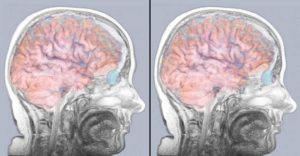

Появление отека мозга при инсульте избежать очень сложно, а в некоторых случаях невозможно. Такая патология представляет собой скопление жидкости в нервных клетках, что приводит к увеличению объема внутри черепа. Развитие этого процесса начинается с первых часов заболевания.

Отек головного мозга – это тяжелое осложнение после инсульта, который показывает, насколько сильно поражены структуры мозга. Это состояние вызывает повышение внутричерепного давления, головные боли и нарушение кровотока, что может спровоцировать очередной приступ и привести к смерти больного.

Инсульт повреждает или сдавливает некоторые области мозга, что нарушает работу дренажной системы и приводит к застою вещества, которое отвечает за обменные процессы в клетках мозга. В большинстве случаев отек поражает оба полушария.